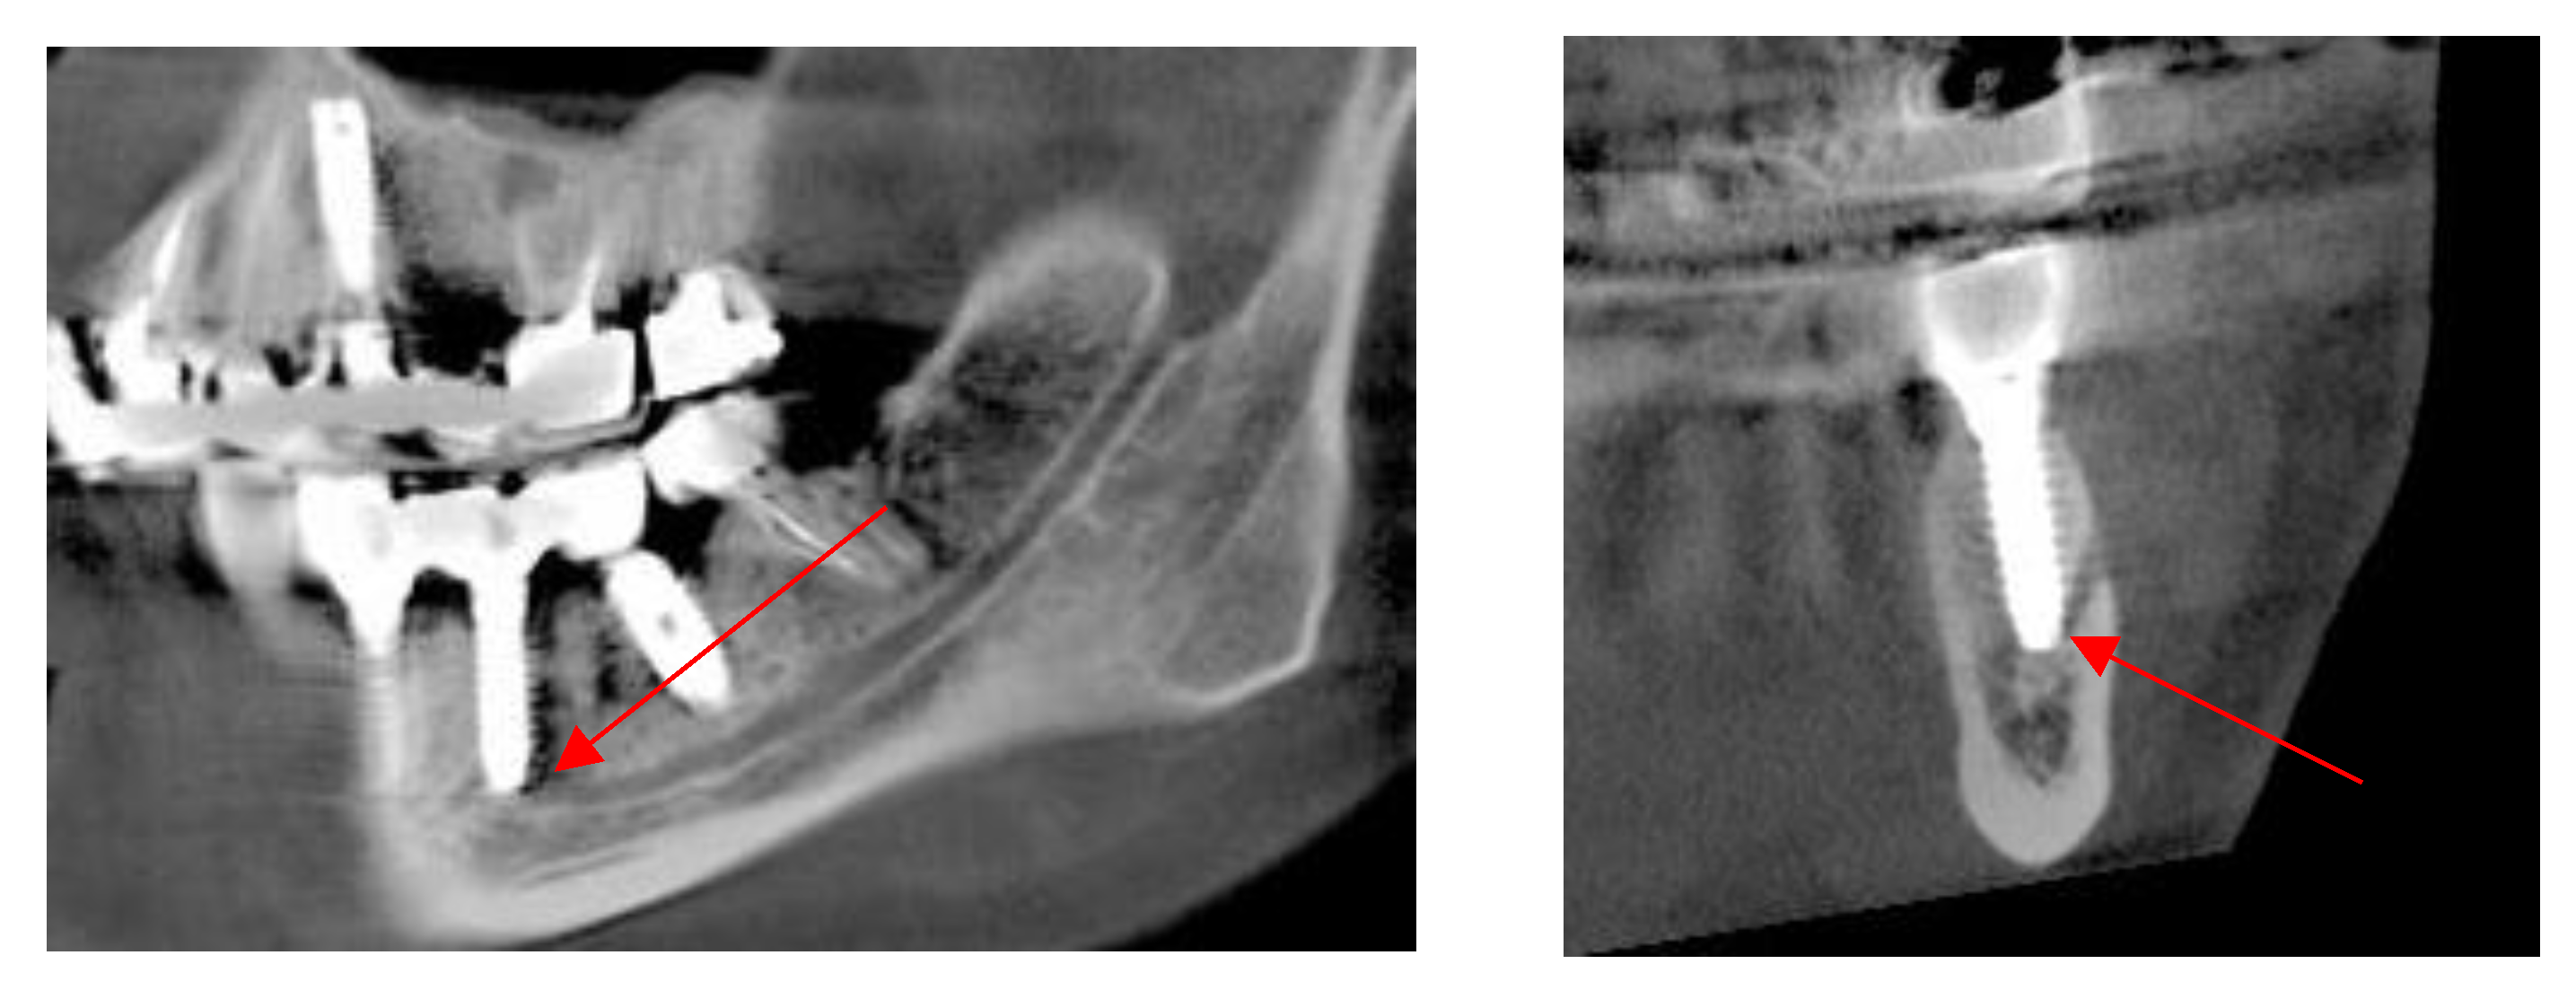

Mandibular Canal

Assessment, Planning and Prevention in the Surgical Context